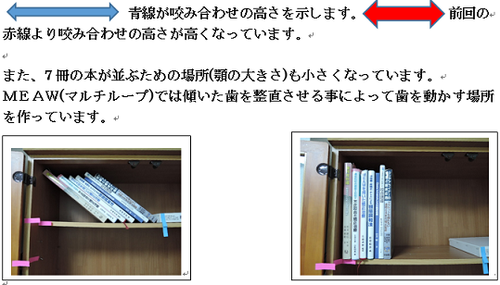

MEAW(マルチループ)を利用して歯を動かす隙間の作り方は2種類あります。

②ふたつ目は以下の様な原理です。

①では歯が近心側に綺麗に傾いた場合ですが、歯が内側(舌側)に傾く事もあります。

この場合もMEAW(マルチループ)によって内側(舌側)に傾むいた歯を起こしていきます。

MEAW(マルチループ)を利用して歯を動かす隙間の作り方は2種類あります。

①ひとつ目は以下の様な原理です。

これを身近な7冊の本を使って説明していきましょう。